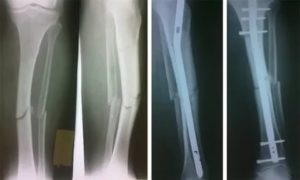

Но с учетом того, что кость опорная и при повреждении ее наблюдается смещение, предпочтение отдается операции.

Сразу же после поступления положено наложить гипс, если перелом без смещения, что встречается сравнительно редко. Когда есть смещение, этапом консервативного лечения или подготовки перед операцией является скелетное вытяжение.

Процедура проводится под местной или общей анестезией, в зависимости от состояния пострадавшего. Через определенный участок (часто это пятка) проводится специальная спица, к которой крепятся грузы. В таком положении пострадавший проводит примерно 6 недель, а после на 4 месяца накладывается гипс.

Если вытяжение не приносит должного результата, то больному назначается оперативное вмешательство, во время которого костные отломки фиксируются с помощью стержней, шурупов, пластин или аппарата Илизарова.

Стержень

В коже пациента производится разрез, сквозь который в канал кости вставляется стержень из медицинской стали. Стержень вынимается, когда кость полностью срастается.